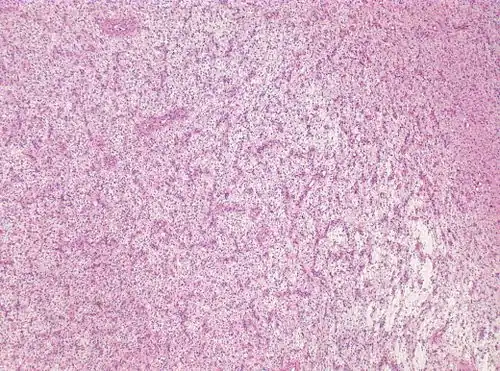

For further confirmation, the clinicians require biopsy and immunohistochemical staining of the resected tumor after surgery. The infiltrative AG cells display positive results for several immunostainings, especially the glial fibrillary acidic protein (GFAP) and epithelial membrane antigen (EMA).[1] Clinicians also observe a specific dot-like pattern from the stained EMA photomicrograph.[3] Other specific AG immunohistochemical tests include Ki-67 proliferative marker, neurospecific nucleoprotein (NeuN), protein 53, synaptophysin (Syn), oligodendrocyte transcription factor-2 (Olig-2) and creatine kinase (CK).[3] In the 2016 WHO classification of CNS tumors, AG is characterised as GFAP-positive, NeuN-positive and low Ki-67 proliferative rate with a perivascular growth pattern.[13]